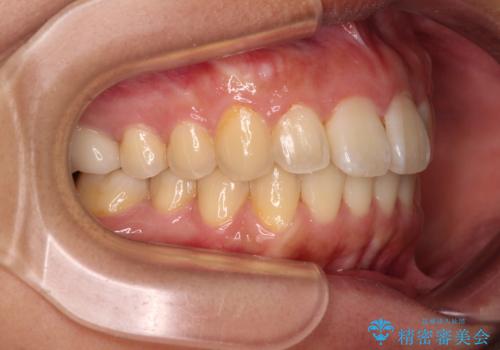

前に出ている前歯を引っ込めたい インビザライン矯正

- 前方に傾斜した上下の前歯を気にして来院された患者様です。

唇の閉じにくさや横顔のシルエットが気になるような突出感ではなかったため、インビザラインを用いて、歯列の遠心移動とIPR(歯と歯の間を削る)により前歯の傾斜を改善していくこととしました。

スムーズに終了すると思われましたが、インビザライン矯正独特の奥歯が咬み合わない状態が続き、更には遠方へ転居されたこともあり、治療期間は長引いてしまいました。